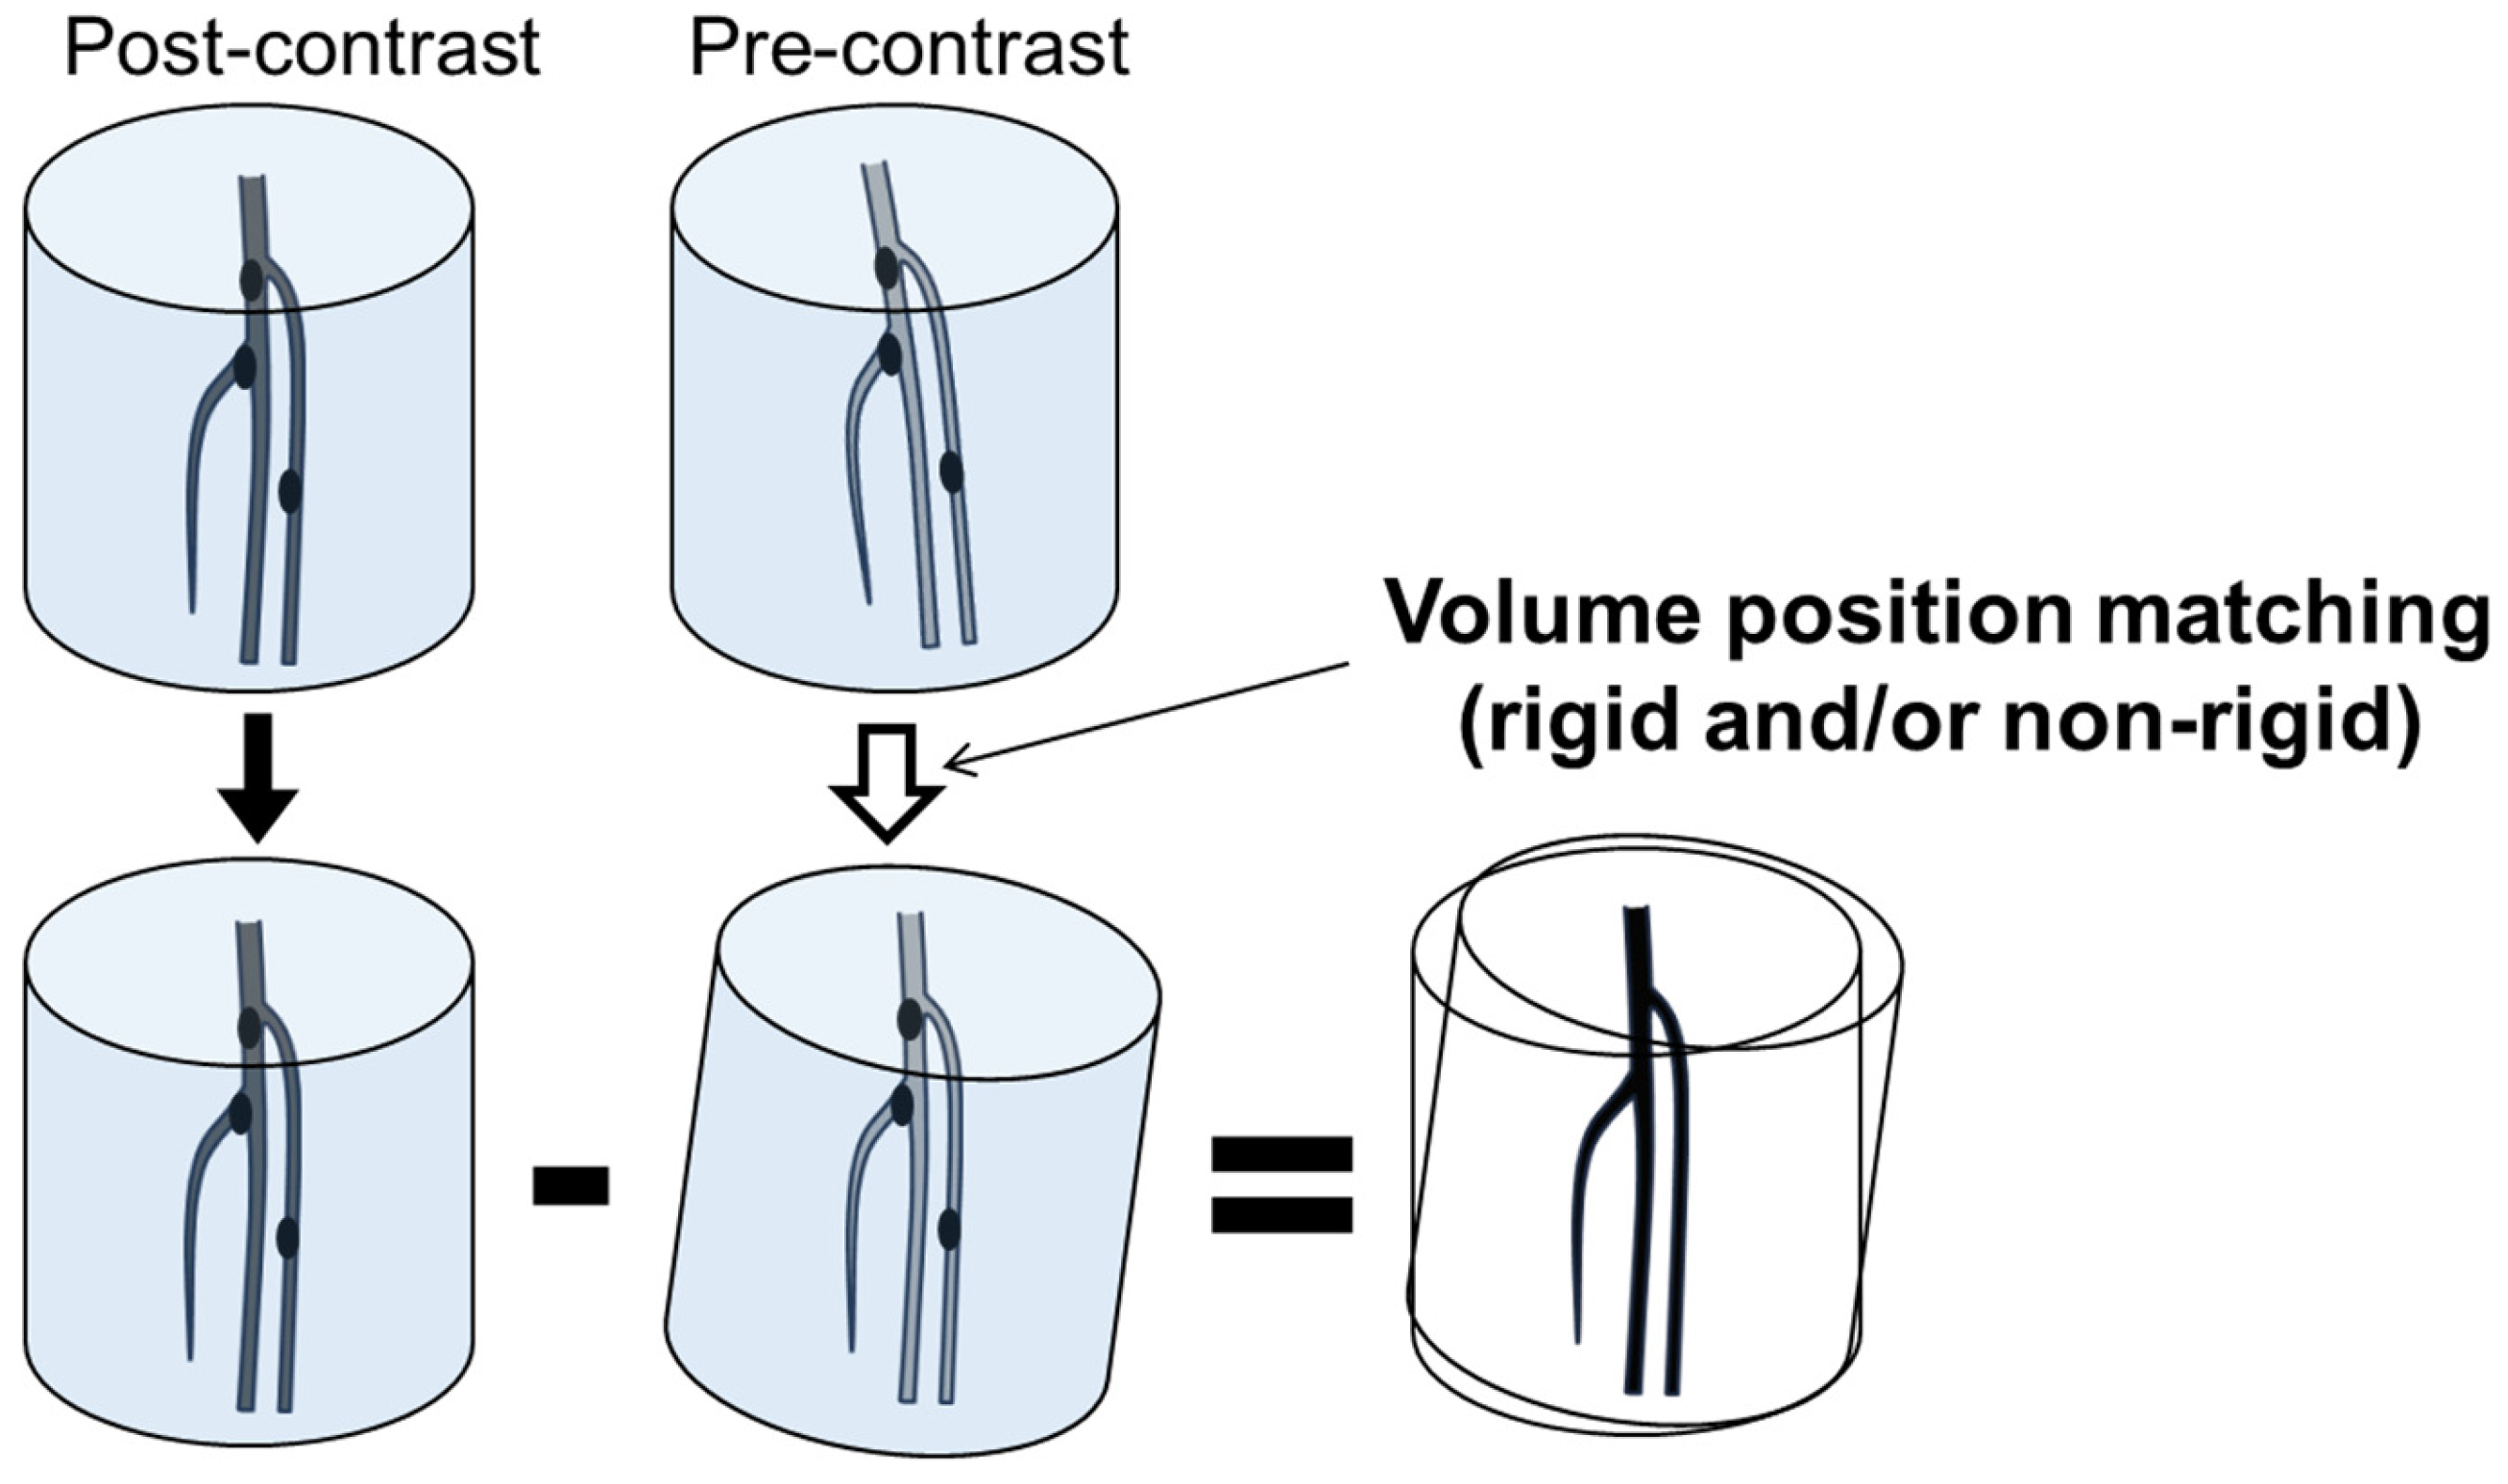

2.2. CT Angiography